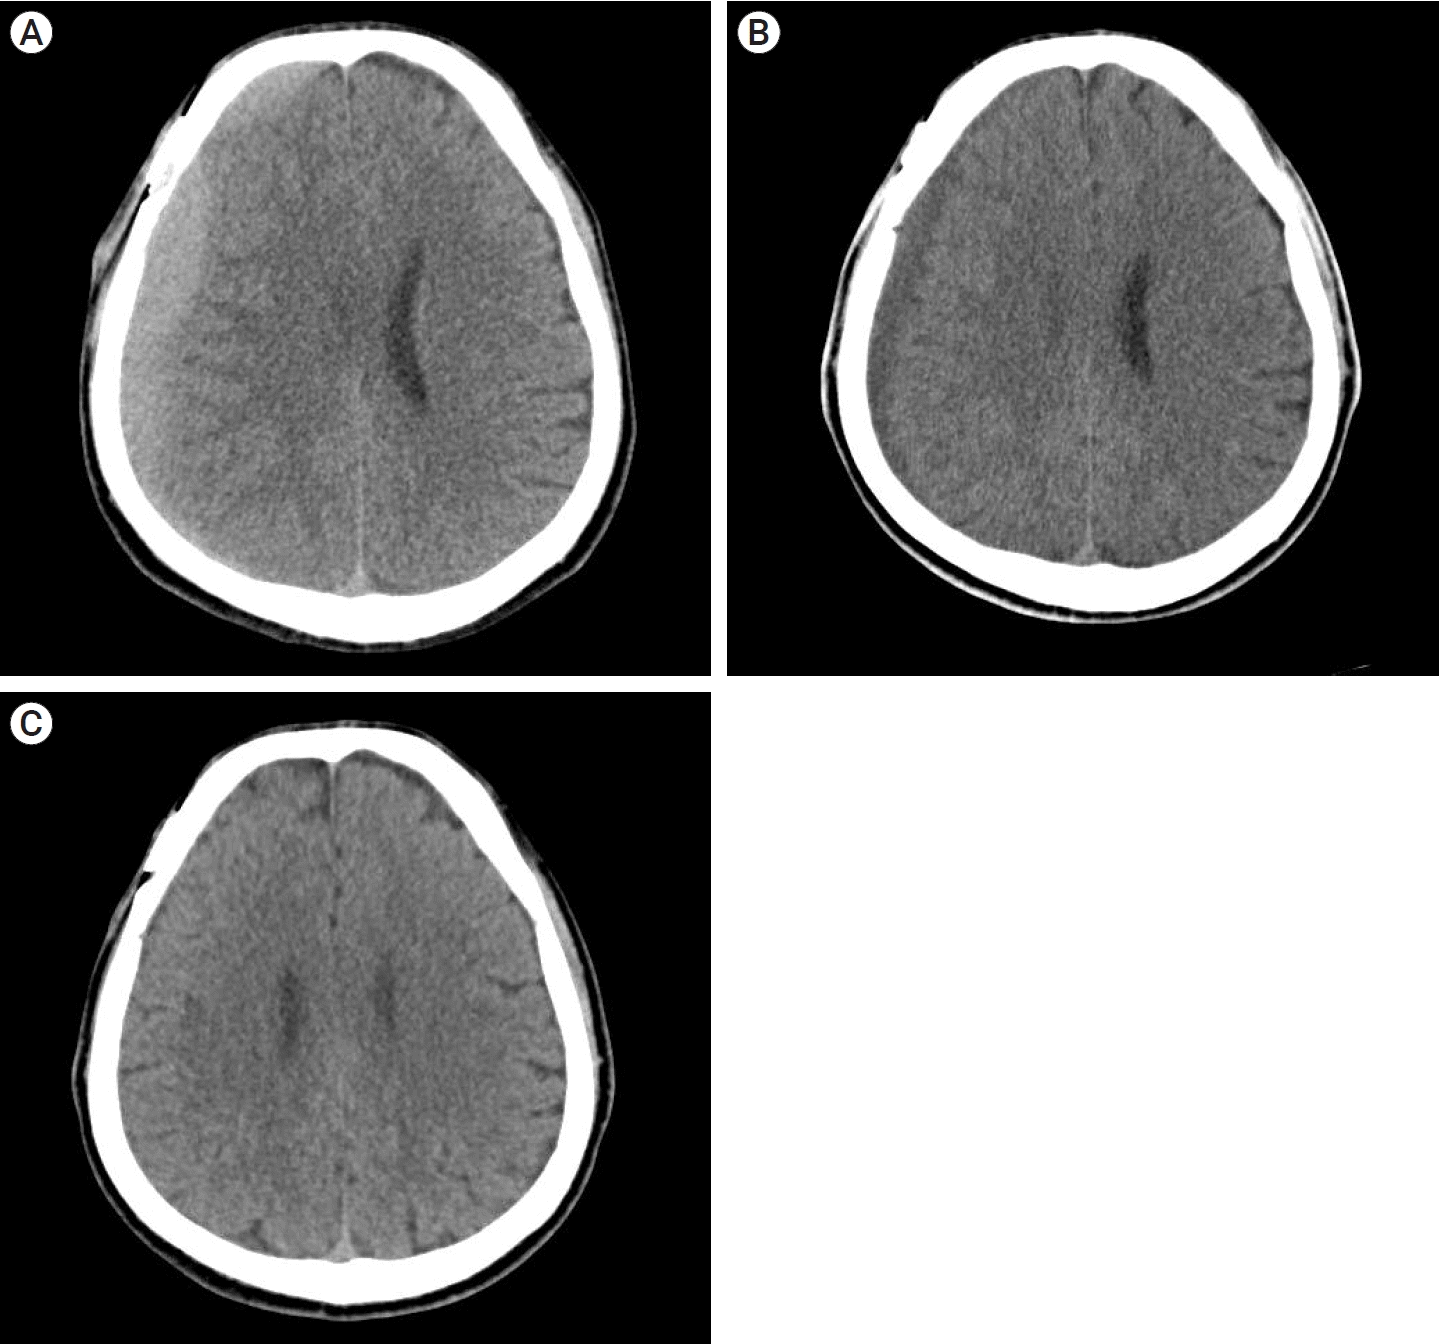

A 68-year-old man was treated with surgical clipping for unruptured right MCA bifurcation and right posterior communicating artery aneurysms. The patient was taking medications for hypertension but was not taking antiplatelet agents. The surgery was performed through ipsilateral pterional approach, and the patient was discharged without any neurologic symptom.

A CT taken on the 42nd POD confirmed high-density CSDH in the frontoparietal area (Fig. 4A); volume was 56.3 ml with a maximum thickness of 9.44 mm, HUs of 59.51, and midline shift of 3.26 mm. A prominent linear low-density area was observed between the hematoma and the brain cortex (Fig. 4B). The patient was observed to be mildly symptomatic (MGS=1) and only had a mild headache (NRS=2), which was easily relieved by acetaminophen. The patient was scheduled for an outpatient visit two weeks later.

A CT scan on the 60th day after surgery showed the hematoma had become iso-dense and decreased in volume compared to the previous scan, and the patient’s symptom was also improved. (Fig. 4C); volume was 43.1 ml, HUs was 41.53, maximum thickness was 9.2 mm, and midline shift was 3.23 mm. The third CT scan, taken 112 days after surgery, showed complete resolution of the hematoma (Fig. 4D).

Fig. 4.

(A) CT scan showing a high-density CSDH in the frontoparietal area (Hematoma volume: 56.3 ml, maximum thickness: 9.44 mm, HUs: 59.51, midline shift: 3.26 mm). (B) CT scan of 2nd OPD showing a decrease in the amount of hematoma, and a linear low-density area between the hematoma and the brain cortex was still observed. (C) CT scan of 3rd OPD showing that the hematoma had become iso-dense (Hematoma volume: 43.1 ml, maximum thickness: 9.2 mm, HUs: 41.53, midline shift: 3.23 mm) (D) CT scan of 4th OPD showing complete resolution of CSDH. CT, computed tomography; CSDH, chronic subdural hematoma; OPD, outpatient department; HU, hounsfield units